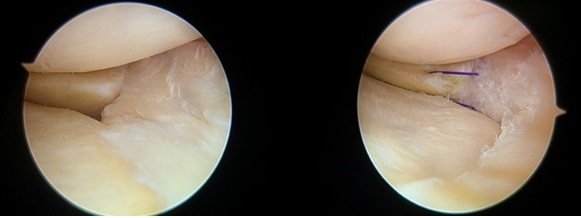

오히려 파열 위치에 따라서는 지속적으로 무릎을 사용하게 되면 파열 부위가 점점 커질 수 있어 파열의 크기가 크거나 파열이 진행될 가능성이 높은 위치라면 관절경을 이용한 수술적 치료를 시행하는 것이 표준 치료로 정립돼 있다.

따라서 가장 이상적인 치료는 파열된 부분을 봉합하는 것이다.

다만 대부분의 파열이 반월연골판의 혈관이 없는 부위에 발생하기 때문에 봉합을 하더라도 붙지 않을 가능성이 많고, 반월연골판 자체가 노화에 의해 변성이 진행되어 파열된 퇴행성 파열, 여러 방향으로 파열된 복합 파열이나 파열 후 오랜 시간이 지난 진구성 파열은 봉합술이 어렵고 불가능한 경우가 많다.

수술적으로 봉합해도 치유되지 않을 부위를 단순히 봉합하는 것은 결국 수술 부위의 재파열로 이어질 가능성이 매우 높기 때문에 이러한 경우는 파열된 반월연골판 절제술을 시행하게 된다.